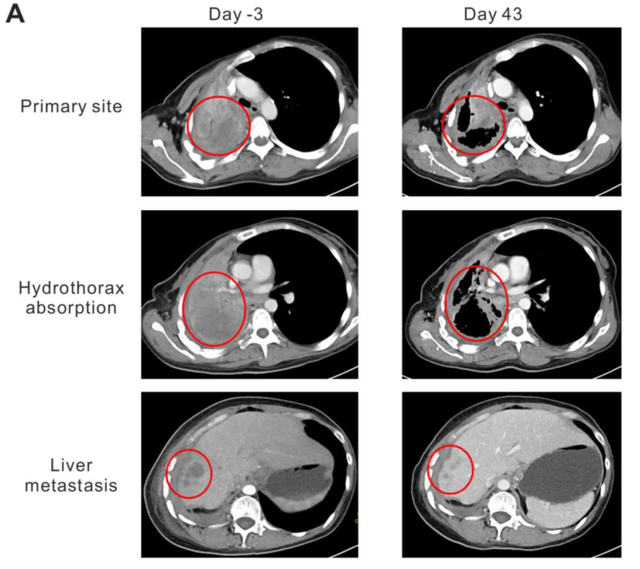

在绝望之时,窦女士意外得知TCR-T细胞疗法,于是毅然加入TCR-T细胞的临床研究。幸运的是,窦女士这次治疗很快显示出效果,胸痛明显减轻,止痛药只要吃一半的量就起效,气短消失,咳血也停止了,肿瘤标志物下降超过一半。治疗后1个月复查时,发现肿瘤明显缩小,原肺病变大小从95×86×54mm减少到64×44×54mm。胸水显著减少,治疗前完全阻塞的右肺部分张开,肝上的肿瘤也从 19.8×19.6×20mm减少到10×10×10mm。

图片源于Oncology Letters